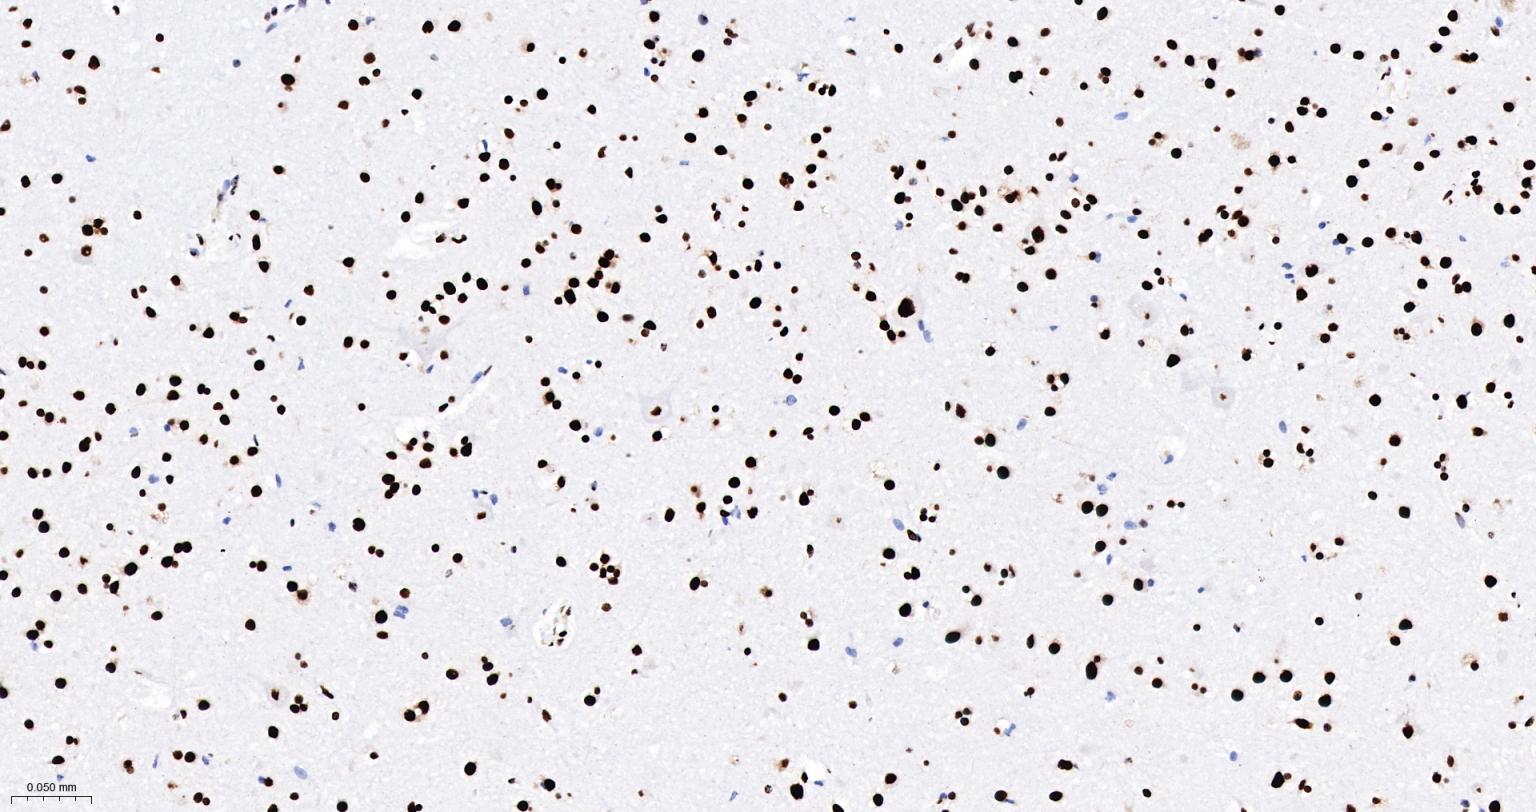

Paraformaldehyde-fixed, paraffin embedded Rat Cerebrum; Antigen retrieval by boiling in sodium citrate buffer (pH6.0) for 15 min; The section was incubated with DDX9 Monoclonal Antibody, Unconjugated (bsm-61787R) at 1:200 overnight at 4°C, followed by conjugation to the bs-0295G-HRP and DAB (C-0010) staining.